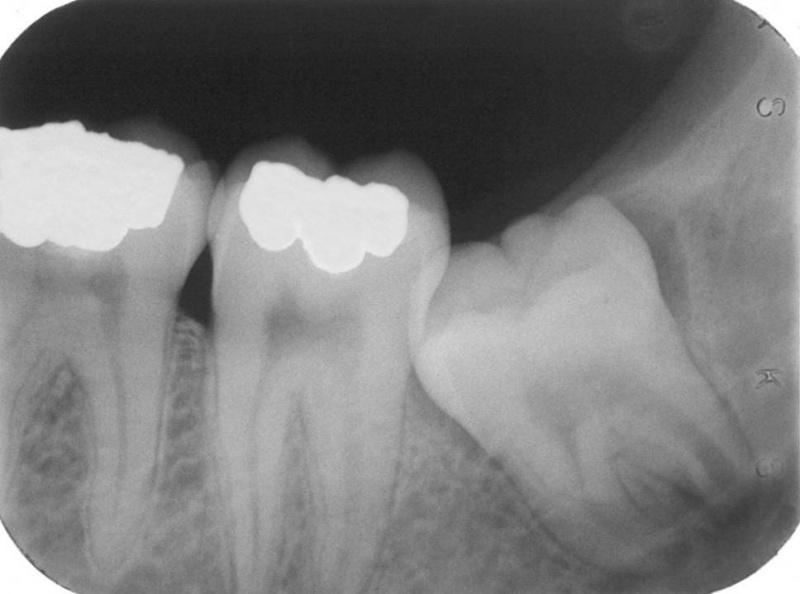

• Radiographs